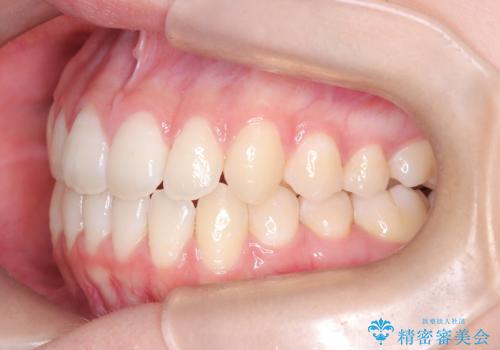

- 右上の小臼歯が大きくねじれており、噛み合わせや見た目に影響を与えている状態でした。診察の結果、インビザライン単独では十分な回転が得られにくいと判断。そのため、基本的な歯列の移動はインビザラインで行いながら、部分的にワイヤー矯正を併用するコンビネーション治療を計画しました。

まず、インビザラインで歯列全体を整えながら、スペースを確保しました。その後、部分ワイヤーを装着し、右上小臼歯の捻転を効率よく改善。ワイヤーの力を活用することで、より確実に歯の向きを整えることができました。治療後は、「しっかり噛めるようになり、見た目も自然になった」と患者様にもご満足いただきました。